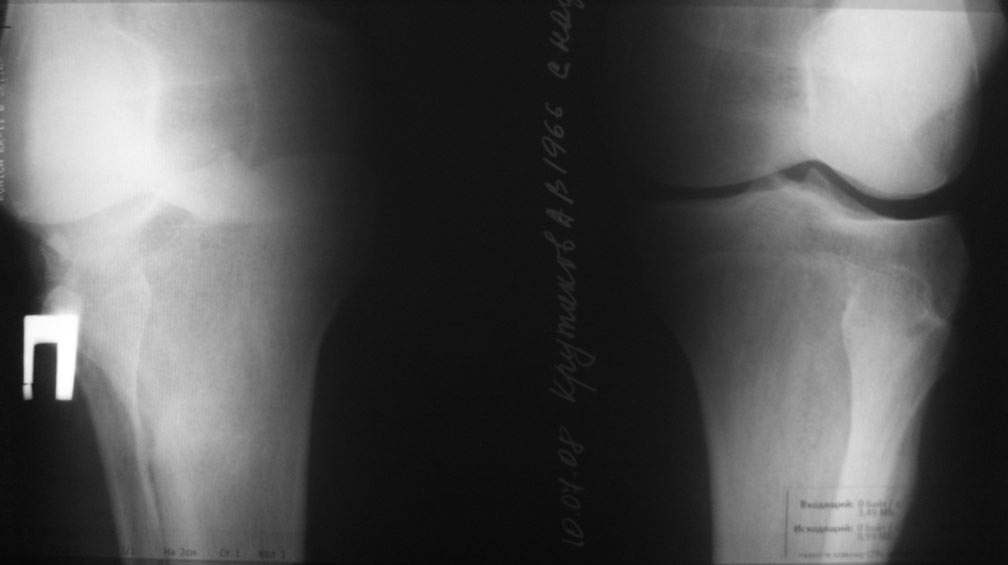

Пациент наконец то объявился вновь, и мы смогли выполнить новые снимки как лежа, так и в нагрузке.